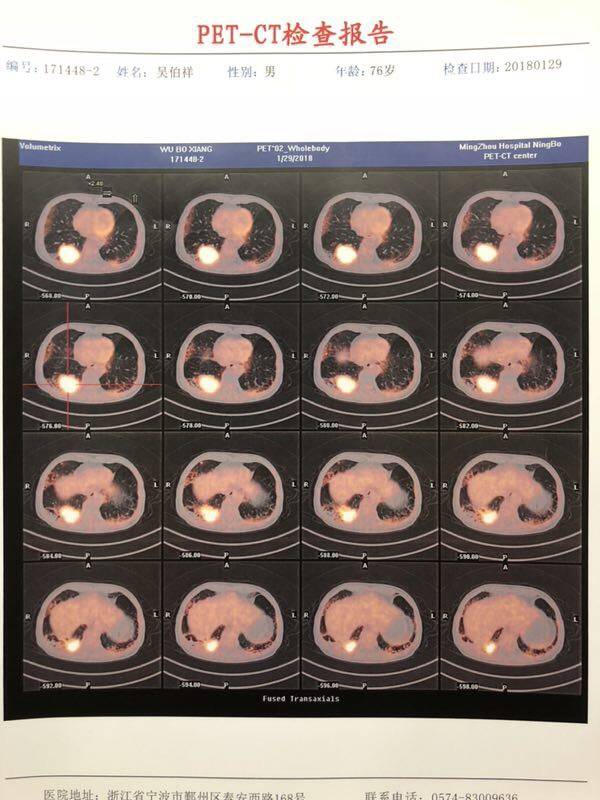

大年三十先给大家拜个早年、祝大家新年快乐、健康平安、幸福永远!因近日忙又累没有及时分享!抱歉!使用九次O后换了I,12号已注入!贴上四张这次PET的影相片子、PET报告单是很厚的一本就不一张张拍上了!再贴上使用O前后两次PET的报告单总结、四次后之八次后的肿标变化和其它检查!以供需要的朋友参考!换药理由:经过进一步检查医生确定O没有耐药、对主灶继续有效、原来粘连侵润胸膜的一片基本脱离、主灶比之前有小、活性也比之前较低很多、医生判断主灶里面白细胞聚多!但在右下胸膜出现新灶(已确定是新肿瘤灶),但O对此新灶无能为力!医生建议四个方案、其中两个是联药、两个是单药、考虑到不管是多温柔的联药方案、副作用都是不可避免的、和医生沟通商仪、决定还是先上温柔的I吧、过年了、平平安安过个年!希望I也给力、接好O的棒!再说下我们九次O的副作用:九次O全程没有什么特别副作用、这点不得不给O赞一个、就是乏力疲劳肌肉酸痛、不过不严重、老爸还经常去钓鱼!效果:四次时评估效果棒肿瘤比使用前小一半、肿标也下来一大半!八次评估时比四次时进展0.5,肿标也上去了!刚开始考虑是耐药了、故又做了PET、医生经过PET判断、没有耐药、但需要处理新灶的特异性、所以只能换方案!还有敏感肿标其实是非常有参考价值意义的、我们四次后效果那么好、至使我得意忘形飘飘然、松懈了下来、以至于在四次评估后至八次评估之间只做了一次肿标、那次肿标211还是继续下来的、但SCC上了0.1,自从使用PDI后我们这两肿标一直往下走的、那次SCC没有下来当时我心里有过嘎瘩、但当时我人还在上面飘着、被我疏忽了没有引起我太大注意、结果八次评估时进展、两肿标全部往上走了、其实那次SCC涨了0.1已经是在提醒我了、但飘着呢无法着落(我们211、SCC就这两种标特别敏感,我们的CEA很幽默、使用PDI前一直正常范围、使用第一次后就往上串了超出正常范围、后来又慢慢下来了),然后八次后我又做了两次肿标、两次都是又往下走了!O的威力还在继续、O给了我们五个月的高质量生存期、还是很感恩!舍不得离开、但又无奈!另外这两次C反应一直往上串、体感和原来一样没有变化、医生判断是新灶做怪、先观察!I药已打进去三天了、第二天怕冷畏寒、不过昨天已经好转、怕冷可能是它的副作用吧!往后我还继续一如既往的分享我们的免疫治疗经历、希望能帮到需要的患友!期望I给力🙏再接再厉怒超O